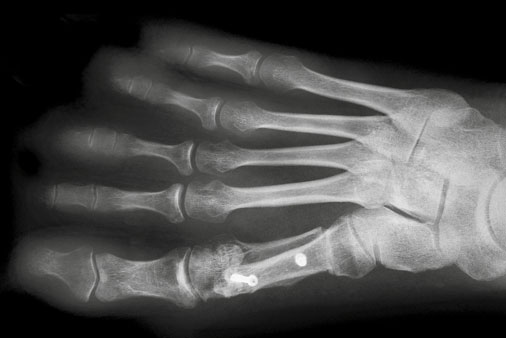

Bei stärkerer Fehlstellung wird die Operation nach Scarf angewendet. Durch den über eine lange Strecke verlaufenden Sägeschnitt ist das Korrekturpotential größer, die langflächige knöcherne Kontaktstrecke bietet eine gute Voraussetzung für eine optimale Knochenheilung. Bei der basisnahen Umstellung erfolgt eine Neuausrichtung der Achse des ersten Strahls im Bereich der Basis des Mittelfußknochens.

Hallux valgus nach Scarf-Operation im Röntgenbild